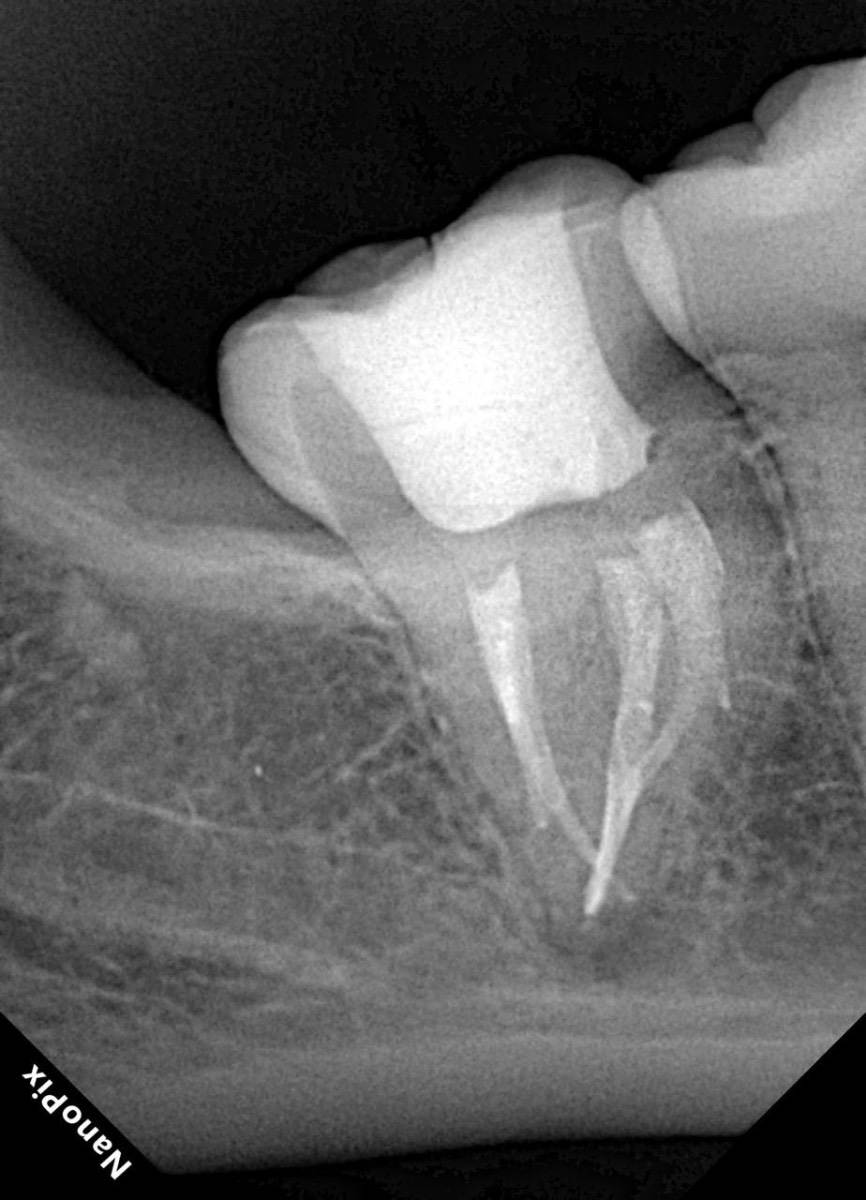

Гарриевич Опубликовано 31 января Автор Поделиться Опубликовано 31 января Когда в твоем кресле оказывается пациент с редким заболеванием «стоматолог-терапевт» работать всегда… легче. Именно! Потому что ты на 100% уверен, что этот человек понимает разницу между «гарантия» и «прогноз», а он на 100% уверен, что ты тот кто ему нужен. Зуб 4.7 со сложной анатомией, ступенькой в мезиальной системе, двойным изгибом, пропущенным каналом и апикальным периодонтитом. Реколл 1 год И сам осмотр через 1 год 4 1 1 Ссылка на комментарий

Гарриевич Опубликовано 13 марта Автор Поделиться Опубликовано 13 марта (изменено) Изменено 13 марта пользователем Гарриевич 2 1 1 Ссылка на комментарий